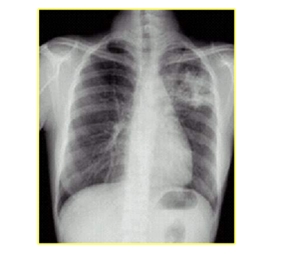

三、肺結(jié)核病

結(jié)核關(guān)鍵詞:低熱、盜汗、乏力、體重減輕

影像學關(guān)鍵詞:肺尖、空洞、鈣化、啞鈴

| 肺結(jié)核類型 | 影像學表現(xiàn) |

| 局限性斑片狀模糊影 | 好發(fā)于上葉尖后段及下葉背段 |

| 干酪性肺炎 | 肺段或肺葉實變,呈大片致密影,邊緣模糊,密度不均,急性空洞表現(xiàn)為“蟲蝕樣” |

| 結(jié)核性空洞 | 多數(shù)空洞壁較薄,洞壁內(nèi)、外緣較光滑,空洞內(nèi)一般無液平,空洞周圍常有衛(wèi)星灶 |

| 支氣管播散病變 | 支氣管分布的斑點狀、斑片狀陰影 |

| 血行播散病變 | 散在于兩肺野、分布較均勻、密度和大小相似的粟粒狀陰影;亞急性和慢性病變粟粒大小和密度不一 |

| 增殖性病變 | 斑點狀高密度影,常排列成“花瓣”,邊界清楚,無融合趨勢 |

| 結(jié)核球 | 邊緣清楚的類圓形陰影,密度較高,內(nèi)常有鈣化,周圍可見衛(wèi)星灶 |

| 原發(fā)性結(jié)核灶 | 啞鈴狀病灶 |